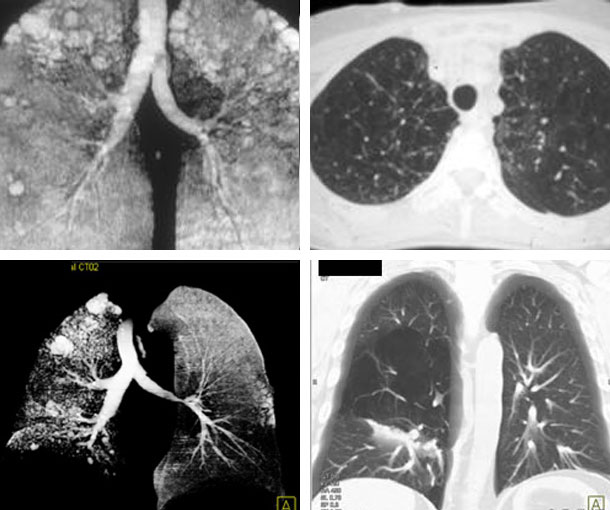

Pulmonary Emphysema CT Findings

- Small or large areas of low attenuation that are evenly distributed

- Ill-defined borders

- Pseudo-wall ~ 1mm thickness

- Vessels in center of emphysema